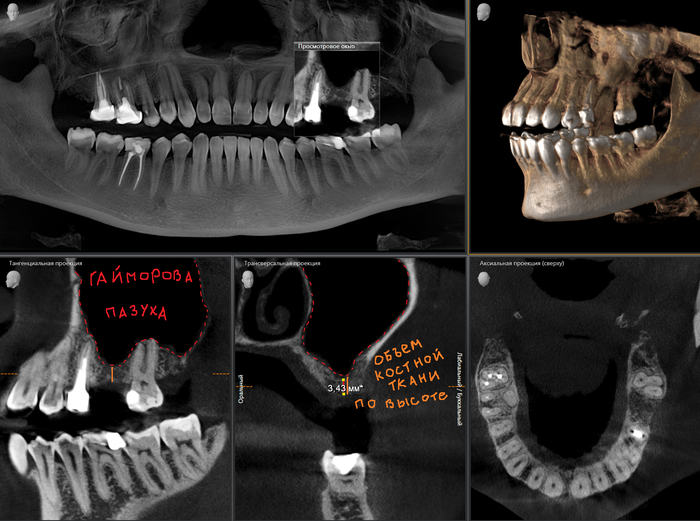

Кроме визуального осмотра, необходимо сделать рентгеновский снимок челюстей. В данном случае простого ОПТГ (Панорамного снимка зубов) будет недостаточно. Потребуется КЛКТ (Конусно-лучевая компьютерная томография).

ОПТГ (Ортопантомограмма) — обзорный снимок зубочелюстной системы. Он является плоскостным, а значит, происходит наложение каждой детали снимка послойно друг на друга. Следовательно, рассмотреть объект исследования (в частности, место планируемой операции), во всех плоскостях (под иным углом или другой проекции) невозможно.

КЛКТ (Конусно-лучевая компьютерная томография) — 3D объемный снимок, напротив, дает нам такую возможность.

Ниже классический пример длительного отсутствия шестого зуба на верхней челюсти слева:

Пример с трехкорневым зубом:

Как мы видим, перегородка в этой области около 3 мм. Данного объема недостаточно для постановки имплантата оптимальной для жевательного зуба длины, следовательно, его нужно увеличивать.